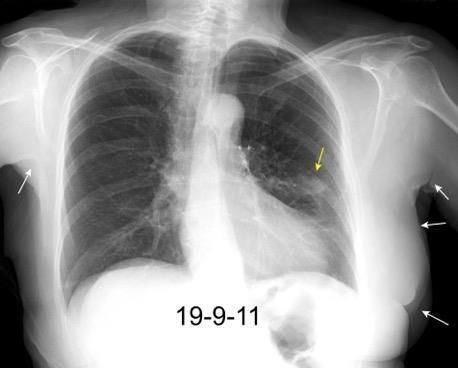

Masa axilar izquierda y derrame pleural derecho. Implantes pleurales, paraespinales . Ganglios en mamaria interna. Linfoma B difuso

2011. Acude por masa axilar

Linfoma NH de cél. B. Invasión Transtorácica.

Afectación axilar

Nódulo en língula.

Cirugía de Ca .de mama hace 23 añosedema de brazo y ganglio en axila. ¡Metástasis!.